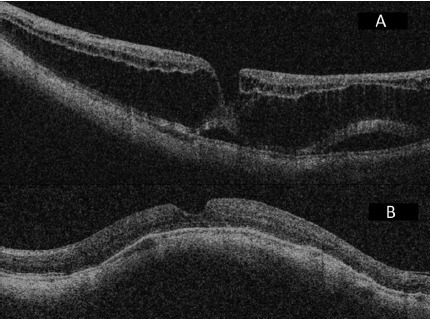

以下为典型患者的术前及术后眼底 OCT 以及 MRI 结果(图 2-8)。

2.png

图 2 A 为 MHMD 患者术前 OCT;B 为同一只眼进行黄斑扣带术加 0.4 cc SF6 气体注射,术后一天 OCT ,视网膜复位,且黄斑裂孔完全闭合(扣带组)